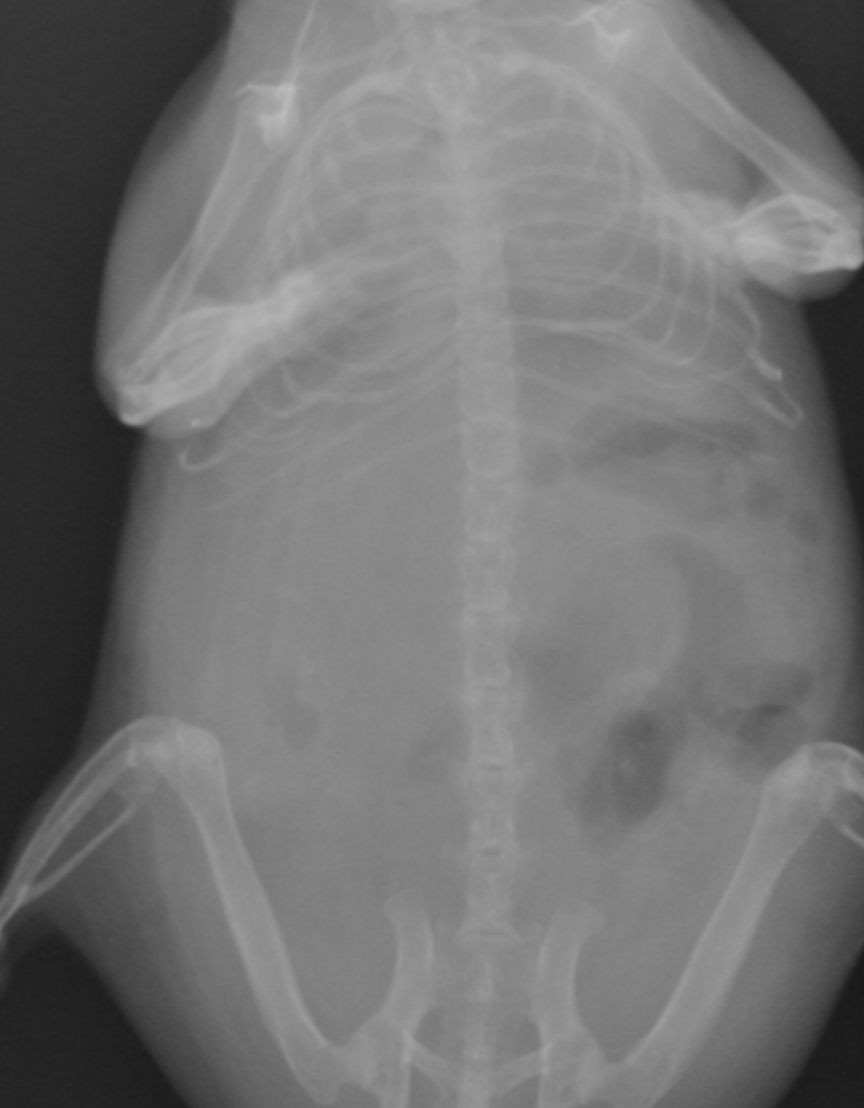

正常例です

正常画像と比べ明らかに心臓が拡大しているのがわかります。また肺の領域も白く見え肺水腫もしくは胸水の存在が疑われます。